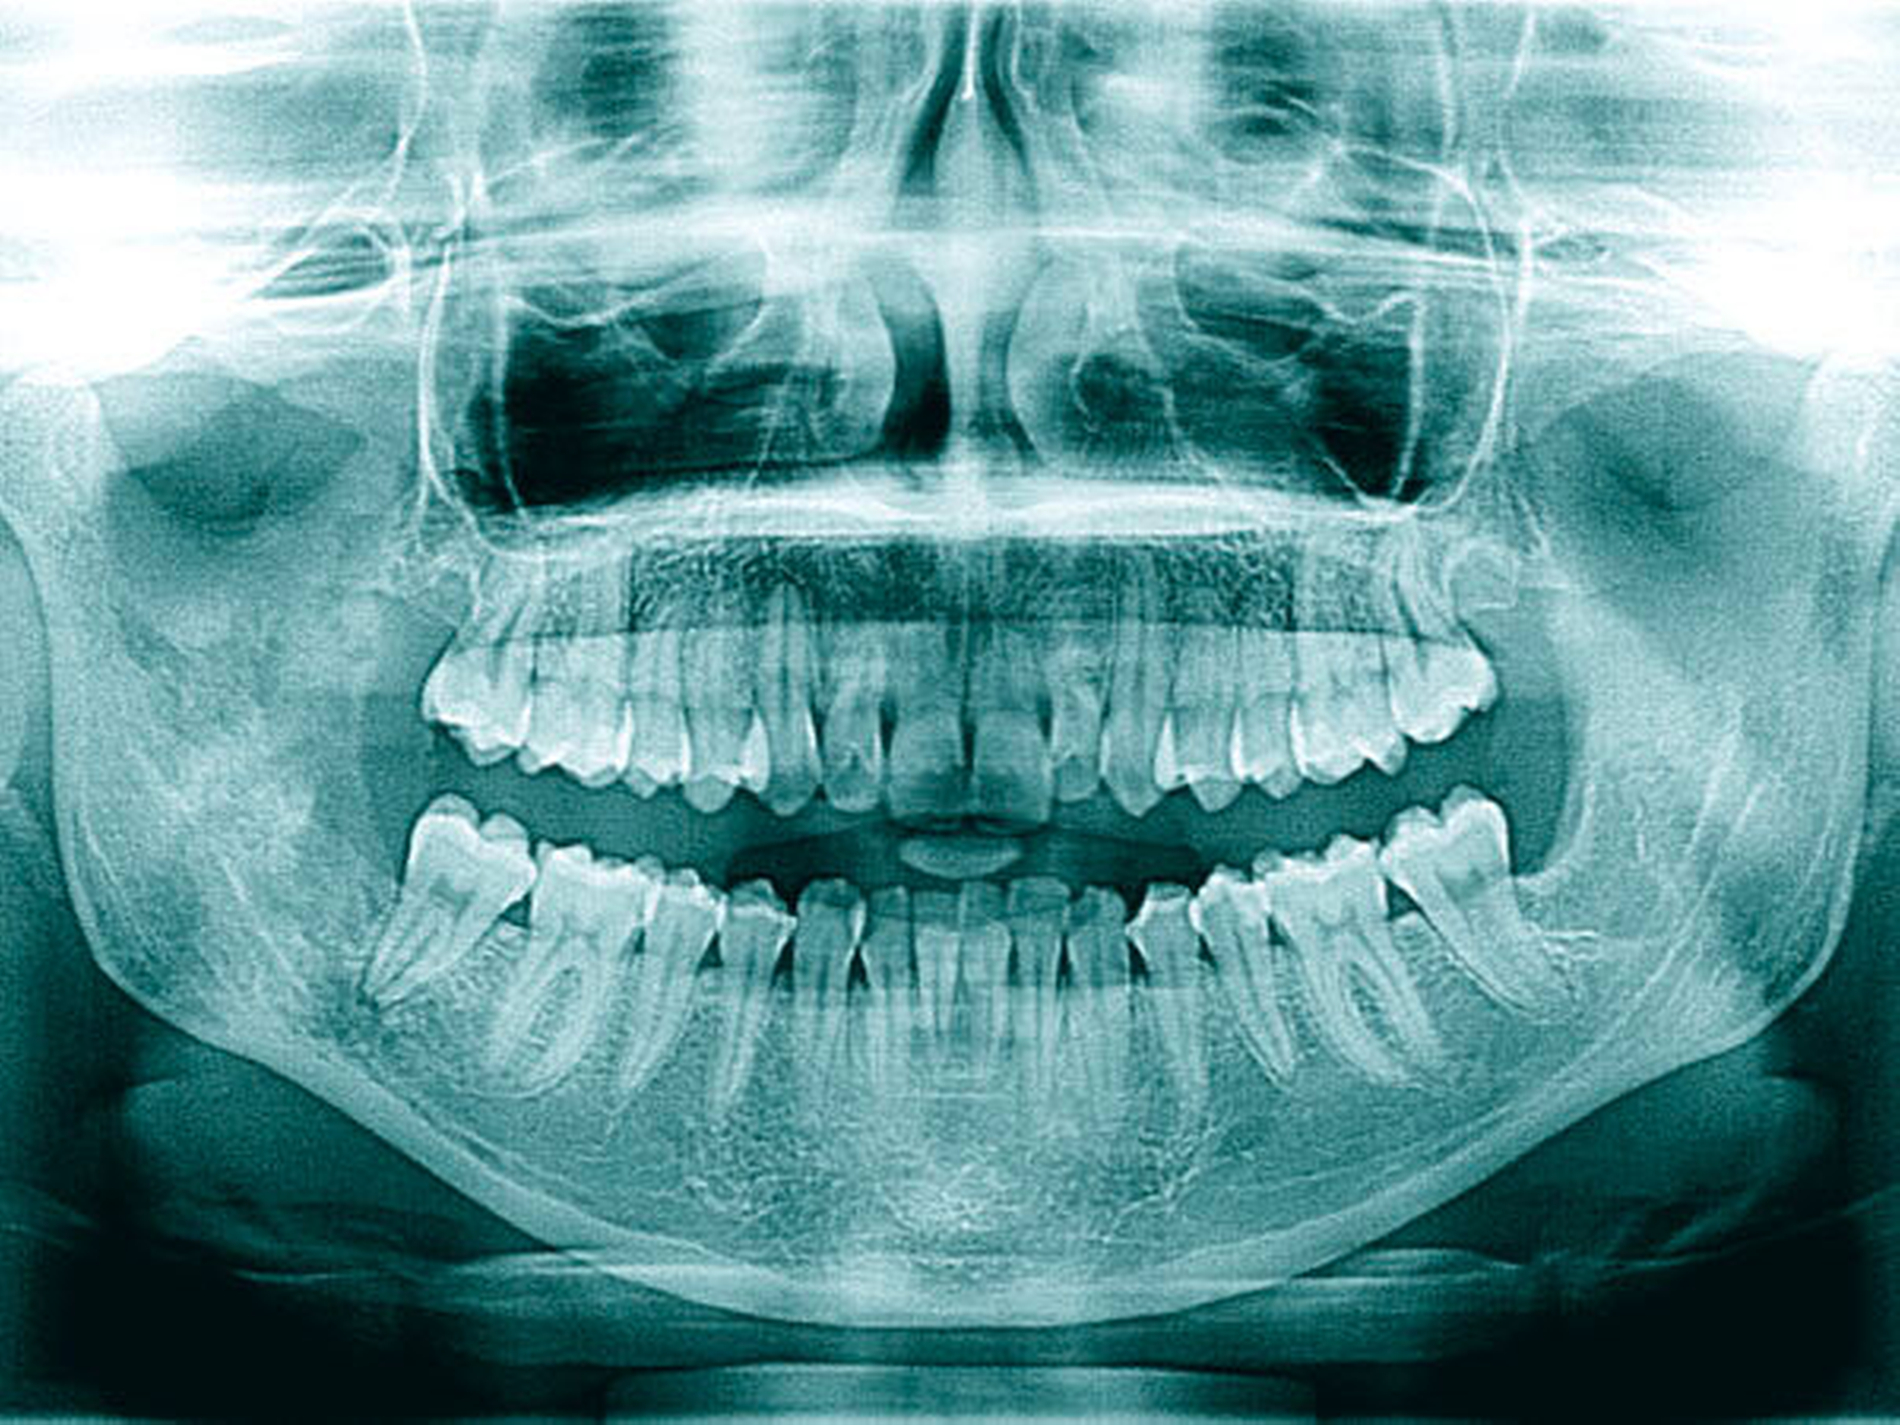

Innerhalb der nächsten acht Wochen, unter laufender oraler Antibiotikatherapie, kam es zunächst erneut zu einer Beschwerdebesserung. Als plötzlich wieder stärkere Schmerzen im Unterkiefer auf der rechten Seite auftraten, zeigte sich im erneuten OPG nun eine Osteomyelitis in regio 048 bis zum Processus muscularis (Abbildung 3). Hier wurde stationär, unter intravenöser Antibiose, die Dekortikation, die Entfernung des gelockerten und schmerzhaften Zahns 47, die Einlage von Gentamycinschwämmchen und plastische Deckung durchgeführt, sowie eine naso-gastrale Ernährungssonde appliziert. Auf eine Kontinuitätsresektion und Anlage einer Reko-Platte konnte zunächst verzichtet (Abbildung 4) werden.